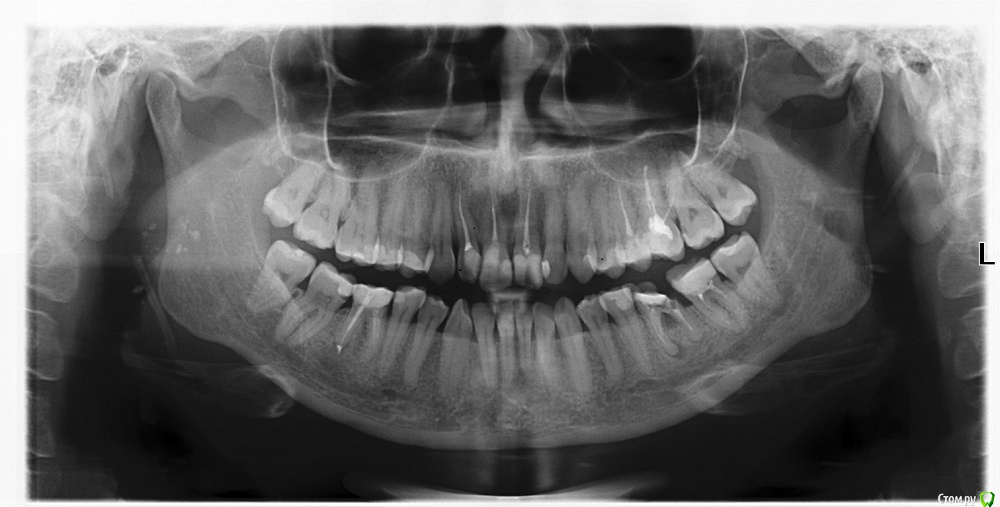

Фотина Опубликовано 18 апреля, 2015 Поделиться Опубликовано 18 апреля, 2015 (изменено) Возможно ли сохранить мои 36-ой и 46-ой зубы?Первый раз зубы лечила много лет назад. В 2014 г. на рентгене обнаружилось хроническое воспаление (кисты?), обломок инструмента и пр. Летом 2014 г. было проведено повторное эндодонтическое лечение: каласепт, пломбирование каналов (где получилось их пройти), депофорез (прицельные снимки после лечения во вложении). Но положительного результата, похоже, добиться не удалось, т.к. в данный момент 36-ой зуб болит при нажатии (46-ой - не беспокоит). Свежий панорамный снимок не показвает улучшений (хотя киста на 46-ом, по-моему, выглядит бледнее, но, ренгенолог сказал, что дело в панорамном снимке) . Что бы Вы могли мне посоветовать (терапевтическое лечение, резекцию, удаление или что иное)? Буду очень благодарна за ответ. Изменено 18 апреля, 2015 пользователем Фотина Ссылка на комментарий

Фотина Опубликовано 19 апреля, 2015 Автор Поделиться Опубликовано 19 апреля, 2015 46 я перелечивала в июне - июле 2014 г., канал запломбировали до верхушки, но киста осталась (видна на панорамном снимке). Еще раз перепломбировывать канал? Ссылка на комментарий